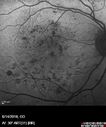

80 year old man has been told that he has swelling in the retina and some bleeding. His vision is pretty good. You asked him to come here for a checkup and possible treatment. He did have laser in both eyes about 6 years ago. He does not want laser VA OD: Dcc20/40-1 NccJ3 VA OS: Dcc20/40-1 NccJ2

Diabetic Macular Edema with Exudates492 viewsPatient did not want injection therapy and did well with laser00000